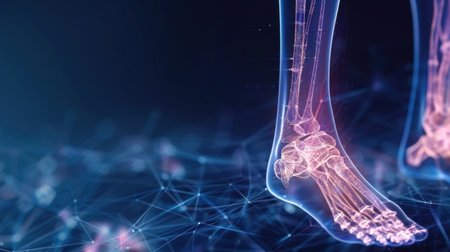

Ankle pain in detail - Sports injuries concept

A detailed digital skeleton of a human foot showing inflammation joint, with vivid red highlights on affected areas set against a dark backdrop for medical learning.

Female foot in pain, highlighted in neon light. 3D rendering

This vibrant x-ray image provides a detailed view of the human ankle joint and foot, showcasing the intricate bone structures and surrounding soft tissues. Ideal for educational and medical purposes.

Running shoes, legs or skeleton bone glow in workout, training or exercise with anatomy pain, body stress or joint burnout. Zoom, runner or sports woman with ankle injury and 3d futuristic abstract

This illustration showcases a human foot anatomy with transparent bones, highlighting intricate structures within a modern digital context for educational and medical usage.

This futuristic digital illustration showcases detailed foot anatomy with neon lines and nodes, symbolizing biological connectivity and innovation in health technology.

Explore the intricate design of human foot anatomy in this futuristic visualization, showcasing bones and joints highlighted with vibrant colors.